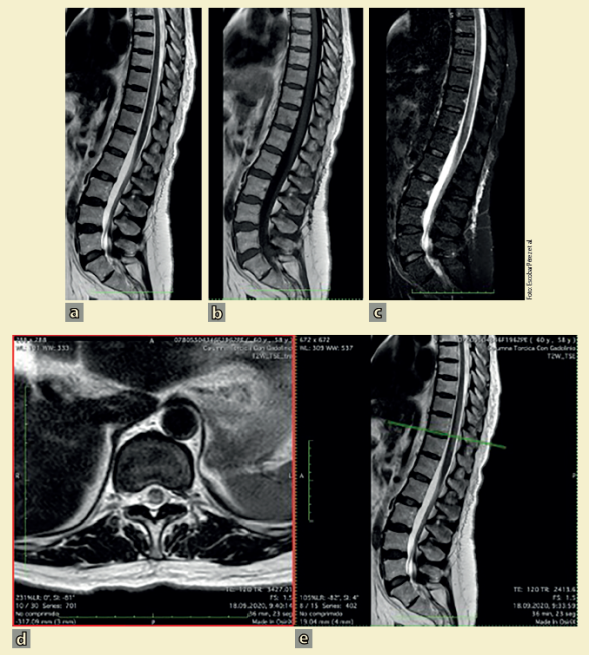

A todos los individuos se les realizó estudio de IRM de la médula espinal; se observó hiperintensidad T2 clásica en la médula espinal y la localización fue central con extensión a lo largo de la mayor parte del diámetro transverso. En la mayor proporción de los 39 pacientes analizados se afectó exclusivamente el subsegmento torácico (44%)14,18-20,22-24,26,30,32-34,37,40-43; en 23% la lesión involucró el subsegmento cérvico-torácico15,17,18,20,26,31,36,38,44; en menor grado fueron el subsegmento cervical (13%)16,17,33,44,45, los subsegmentos cérvico-toraco-lumbar28,46, y toraco-lumbar19,27 en 2 individuos (15%) y solo 1 caso (2.5%) en el subsegmento lumbar21; 1 caso fue difuso21 y en otro caso no se pudo hacer el estudio47. En la mayoría de los individuos (76%) la lesión se extendió sobre 2 o más segmentos espinales, característico de la mielitis transversa longitudinalmente extensa (tabla 1). En algunos individuos las hiperintensidades T2 fueron en parches20,26,31,38),(42, mientras que en la mayoría fueron continuas. Se encontró un caso único de post-COVID-19 con cerebelitis, MTA y polineuropatía desmielinizante inflamatoria aguda, lo que demuestra que la COVID-19 puede provocar daño simultáneo del sistema nervioso central y periférico31. En la figura 4 se muestran las IRM de una paciente mexicana con MTA asociada a la infección de SARS-CoV-2 (comunicación personal; consentimiento informado).

La RM se realizó 8 días posterior al inicio de los síntomas, sin uso de contraste (comunicación personal). a) Secuencia T2 que muestra hiperintensidad correspondiente a la lesión longitudinalmente extensa en segmentos T8-T11. b) Se presenta como isointensa en secuencia T1. c) Hiperintensa en STIR (short tau inversion recovery). d) El corte transversal muestra la lesión y predominio en cordones posteriores, concordante con el predominio en sintomatología propioceptiva de la paciente. Las secuencias fueron obtenidas del centro en el cual se realizó el abordaje inicial y son reproducidas con consentimiento de la paciente (se anexa carta de consentimiento).

Figura 4 Hallazgos en resonancia magnética (RM) de la médula espinal toracolumbar